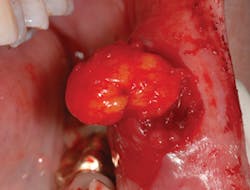

One such entity that is often perplexing to the clinician is the lipoma. (see Figure 1) It is one of the most common total body tumors, yet it is also a rare benign neoplasm not often found intraorally. In order of occurrence when found intraorally, these growths may occur on the buccal mucosa (because of the abundant fatty tissue), the tongue, the floor of the mouth, buccal sulcus, palate, lips, and gingiva (Kumaraswamy et al.2009). They have also been found in the oral pharyngeal area and may interfere with swallowing. This is another excellent reason to critically examine the tonsillar and pharyngeal areas since tonsillar cancer is a prime concern as well.

Lipomas are slow growing, painless, soft, smooth-surfaced, palpable masses, and are noted as having a yellow hue. They are unlike the fibroma, which does not normally present with a yellow-tinged surface and presents a more firm and flesh-toned appearance.

The lesions are broad-based and composed of adipose tissue with an unknown etiology. Some authors report an occurrence of blunt force or soft tissue trauma to the area preceding the development of external lipomas (Aust, et al., 2007). Microscopically, the tissue is covered by a thin layer of epithelium and appears to be normal adipose tissue. The lobules of mature fat cells are circumscribed and thinly encapsulated by a fibrous covering, and are found in a loose fibrous stroma. There is little to no inflammatory component in the lipoma specimen. As evidenced by the tissue found within a container in Figure 2, the specimen will float within the fixative agent giving the pathologist a heads-up on what the submission may contain.